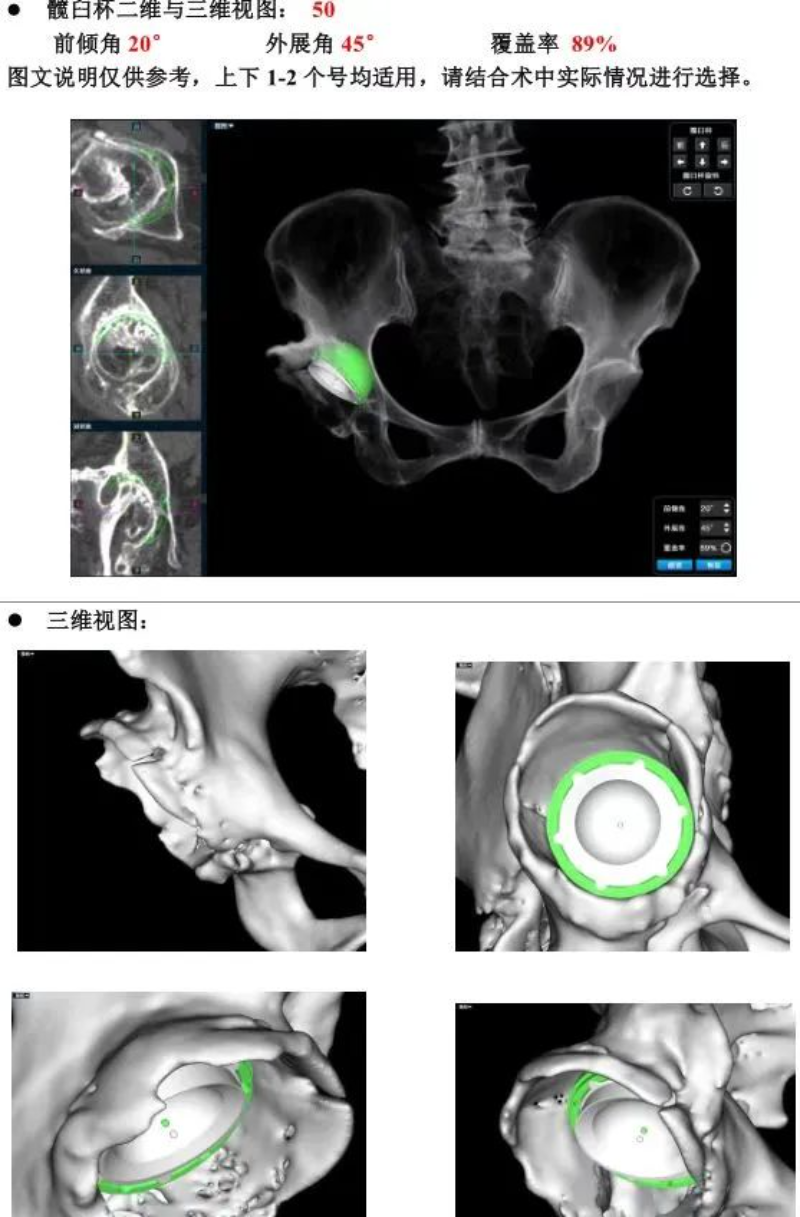

△AI术前策划

50多岁的朱大哥,20多年前因为车祸伤导致股骨头缺血性坏死,一直一瘸一拐走路,就诊时,右侧髋关节股骨头基本消失,髋臼磨损严重,关节已接近融合,肢体短缩有6-7cm,通过术前AI规划,能精准确定截骨的位置,髋臼杯安放的角度和尺寸等。手术进展顺利,术后关节功能恢复良好,肢体短缩明显纠正无神经损伤等并发症,一个月后复查关节稳定,患者从此告别一瘸一拐的日子。